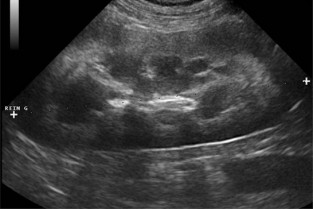

- Un temps d’exposés théoriques sur les principes physiques et contraintes techniques autorisant la reconnaissance des organes abdominaux, l’interprétation des artefacts et des images observées fréquemment chez l’animal sain ou présentant un état pathologique.

- Des travaux dirigés (sur vidéos) de reconnaissance d’images caractéristiques de processus pathologiques et de mise en situation de démarche clinique dans le cadre des modules de niveau avancé.

- lister les principales indications et les limites de l’échographie dans l’exploration de l’appareil urinaire et de l’appareil génital ;

- réaliser un examen échographique de l’appareil urinaire et de l’appareil génital ;

- interpréter les principales images anormales décrites pour ces deux appareils.